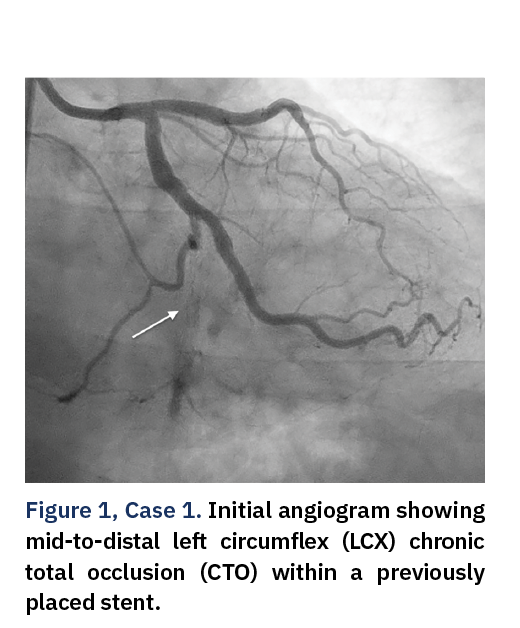

Case 1: CTO of the LCX to LPDA With In-Stent Restenosis in an Old Stent

A 57-year-old male with chronic stable angina and a history of smoking presented with a chronic total occlusion (CTO) of the mid-to-distal left circumflex artery (LCX) extending to the left posterior descending artery (LPDA), involving a previously implanted stent (Figure 1).